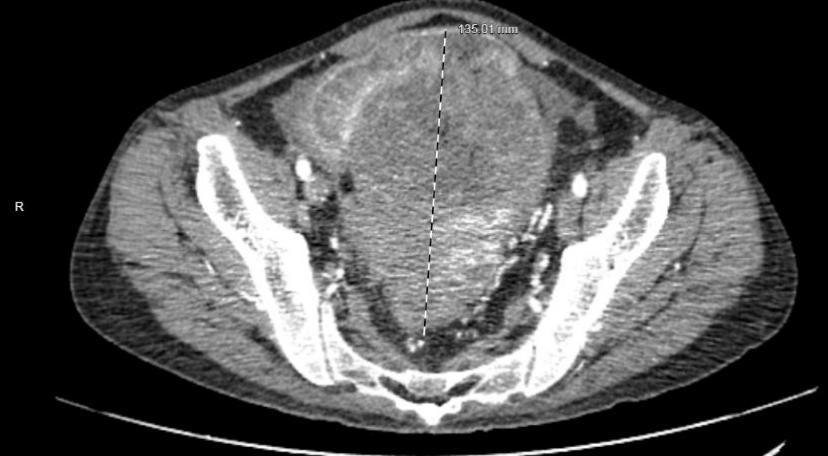

在仔细检查评估后,尹晖明主任发现,胡先生体内肿瘤十分巨大,累及盆腔内大部分脏器,乙状结肠、部分回肠、回盲部、升结肠、膀胱、右侧盆壁等部位,毗邻腹盆腔重要脏器及重大血管主干及分支,合并肠梗阻、中度贫血、低蛋白血症、严重营养不良等多种并发症,手术难度和危险程度相当高。

“患者的肿瘤太大,病变侵及多个器官,与腹膜后大血管分界欠清,如何根治性的切除这么大的肿瘤且尽量保护周围血管、神经,并保证患者远期预后,是手术的难度所在”,尹晖明主任表示。

▲CT下胡先生体内的巨大肿瘤

为确保将手术风险降到最低,经过多学科评估以及周密的围术期管理方案,在患者贫血及低蛋白血症等得到有效纠正的前提下,8月23日,医院普通外科主任尹晖明带领团队医生副主任医师谢承志、主治医师唐曙光、住院医师邓浩进行了“乙状结肠恶性肿瘤根治术+腹腔镜下全盆腔脏器切除手术”,术中见盆腔肿瘤大小约20*16*15cm,如术前所预计的一样,乙状结肠肿瘤累及部分回肠、回盲部、膀胱、右侧盆壁,术中行乙状结肠癌根治+全盆腔淋巴结清扫+部分回肠升结肠切除+膀胱全切。将降结肠与直肠残端吻合,保住患者的排便功能,明显提升了患者术后的生活质量。